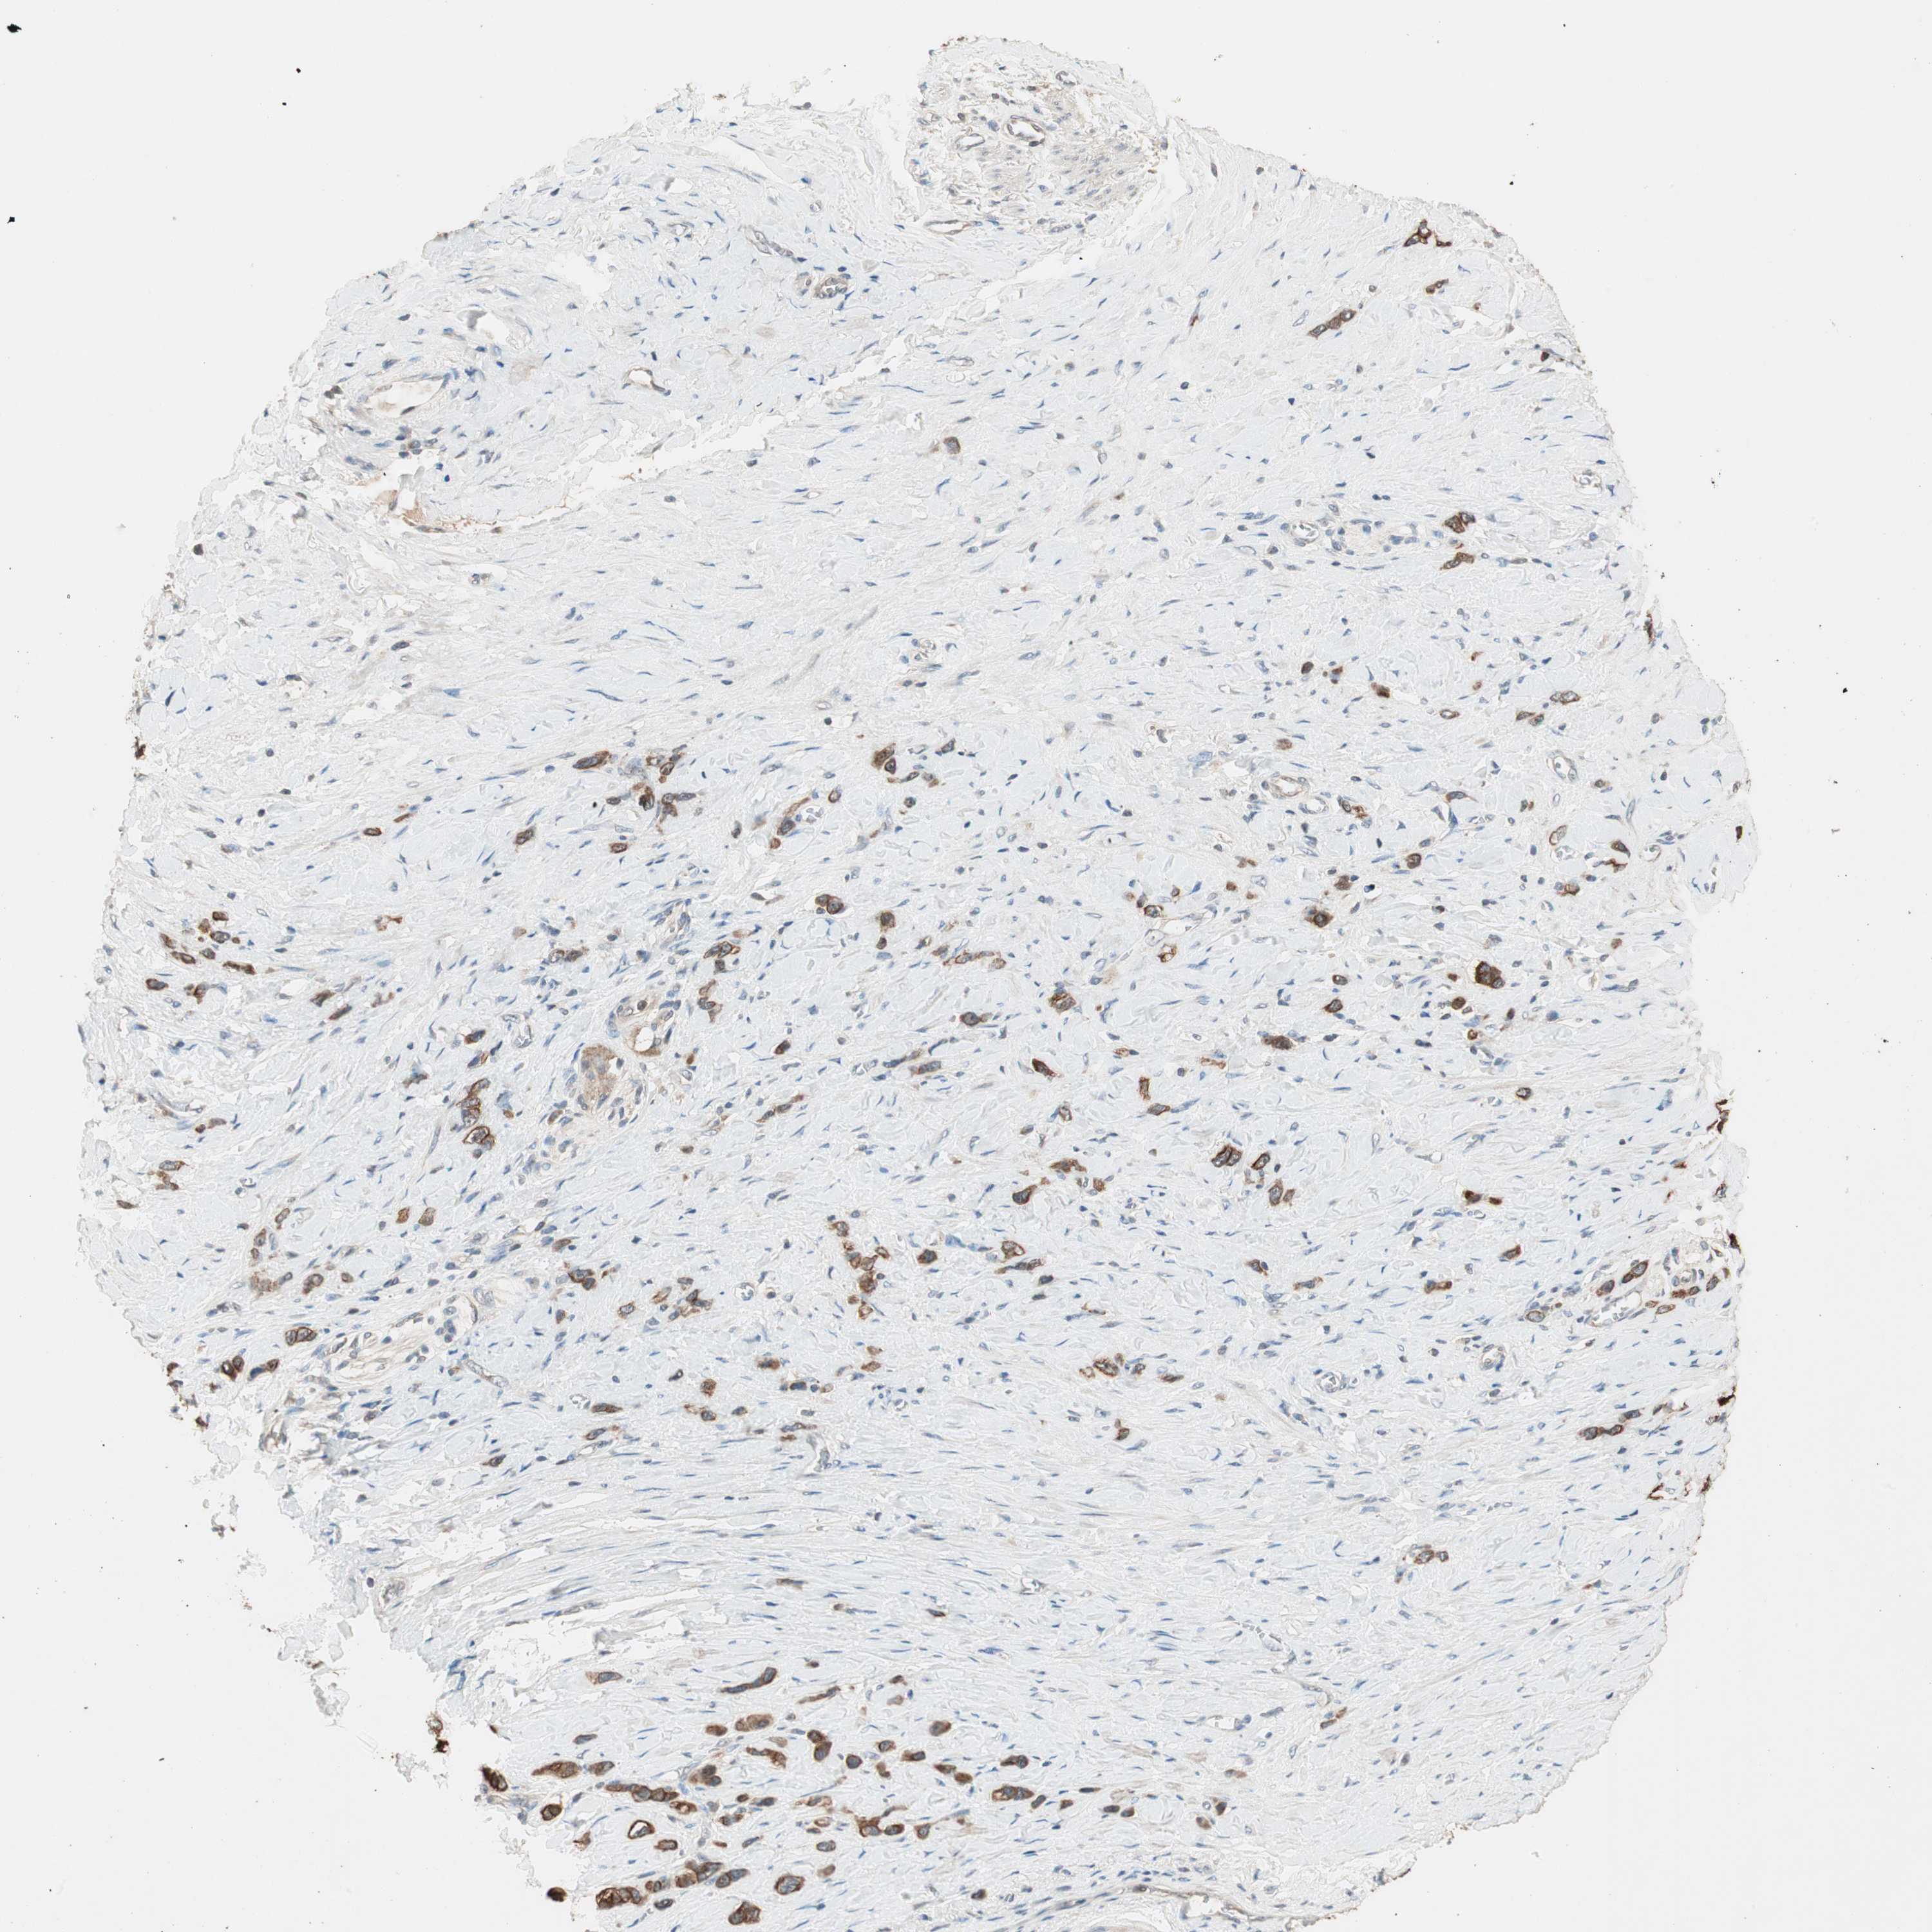

STOMACH CANCER - Protein expressioni

A mouse-over function shows sample information and annotation data. Click on an image to view it in a full screen mode. Samples can be filtered based on level of antibody staining by selecting one or several of the following categories: high, medium, low and not detected. The assay and annotation is described here.

Antibody stainingi

Antibody staining in the annotated cell types in the current human tissue is reported as not detected, low, medium, or high, based on conventional immunohistochemistry profiling in selected tissues. This score is based on the combination of the staining intensity and fraction of stained cells.

Each image is clickable and will lead to virtual microscopy that enables deeper exploration of all samples and also displays staining intensity scores, fraction scores and subcellular localization as well as patient and tissue information for each sample.

Antibody HPA005673

Antibody CAB004566

Staining

High

Medium

Low

Not detected

Intensity

Strong

Moderate

Weak

Negative

Quantity

>75%

75%-25%

<25%

None

Location

Nuclear

Cytoplasmic/membranous

Cytoplasmic/membranous,nuclear

Adenocarcinoma, NOS

Adenocarcinoma, High grade